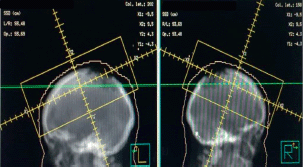

In a multidisciplinary meeting, it was decided to treat with radiotherapy in opposite lateral fields, covering the two lesions of the cranial cap at a dose of 5,100 cGy in 17 sessions at 300 cGy per fraction (Figure 5). Eighteen months later, she is currently under follow-up, resulting in daily healing and complete pain relief (Figure 6).

Figure 5. Opposite lateral treatment field covering the two lesions at 51Gy in 17 sessions with photons.